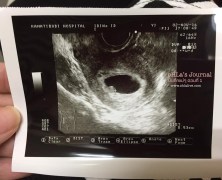

oHLa’s Journal :: บันทึกมนุษย์แม่ ตอนที่ 2 ตรวจเลือดแม่ ดูโครโมโซมลูก

แน่นอนว่าในทางการแพทย์และสาธารณสุขนั้นค่อนข้างแนะนำให้ผู้หญิงเรามีลูกก่อนอายุ 35 ด้วยเหตุผลด้านสุขภาพที่อาจจะส่งผลต่อทั้งลูกและแม่ เมื่ออายุมากแน่นอนว่าภาวะความเสี่ยงต่างๆก็มากขึ้นตาม เรื่องฮอตฮิตติดอันดับหนึ่ง ก็คือ ความเสี่ยงต่อภาวะดาวน์ซินโดรม

oHLa’s Journal :: บันทึกมนุษย์แม่ ตอนที่ 1 กว่าจะท้อง

บันทึกมนุษย์แม่ ตอนที่ 1 …กว่าจะท้อง